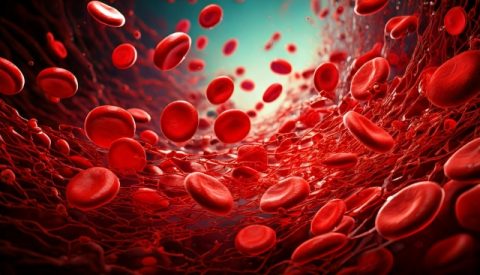

全身の細胞にキレイな血液がちゃんと届き、

栄養や酸素がすみずみに行き渡っていれば、

細胞たちは元気いっぱいですね。

ノーベル生理学・医学賞受賞のドイツの生理学者

「オットー・ワールブルグ」は、

生体内で低酸素状態・低代謝状態で細胞がガン化することを実証し、

がん発生の根本的な原因をすでに明らかにしています。

つまり、ガンとは、全身の「酸素・栄養欠乏状態」の

最も悪化した部分にすぎず、

ガンだけを切り取っても根本的解決にならないのです。